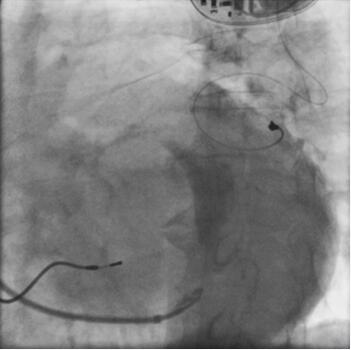

图3-4-15 左室电极断裂

术后患者每6个月随访1次,起搏参数均正常,心功能状况好转。于2010年7月23日随访发现左室电极不工作,阈值和R波振幅测不出,阻抗无限大。将患者收入心内科,胸部X摄片示左室心外膜电极导线在第4肋间处断裂(图3-4-15),考虑再次手术。